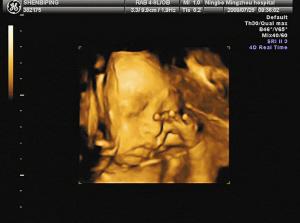

接下来我们一起去看看彩超筛查过程,胎宝宝一些神奇而调皮的举动: 打